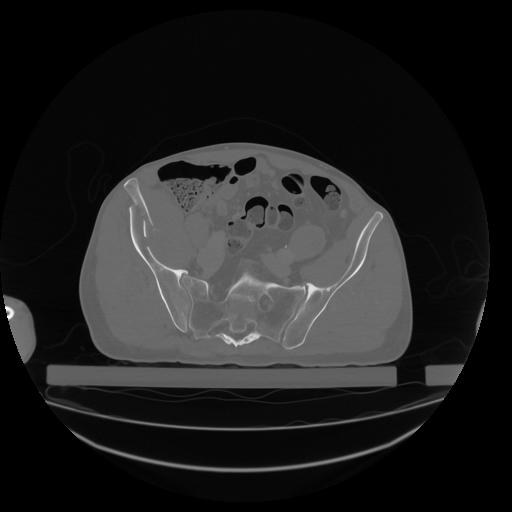

34 CUERPO,CE,Vol,1.0,CUERPO,,